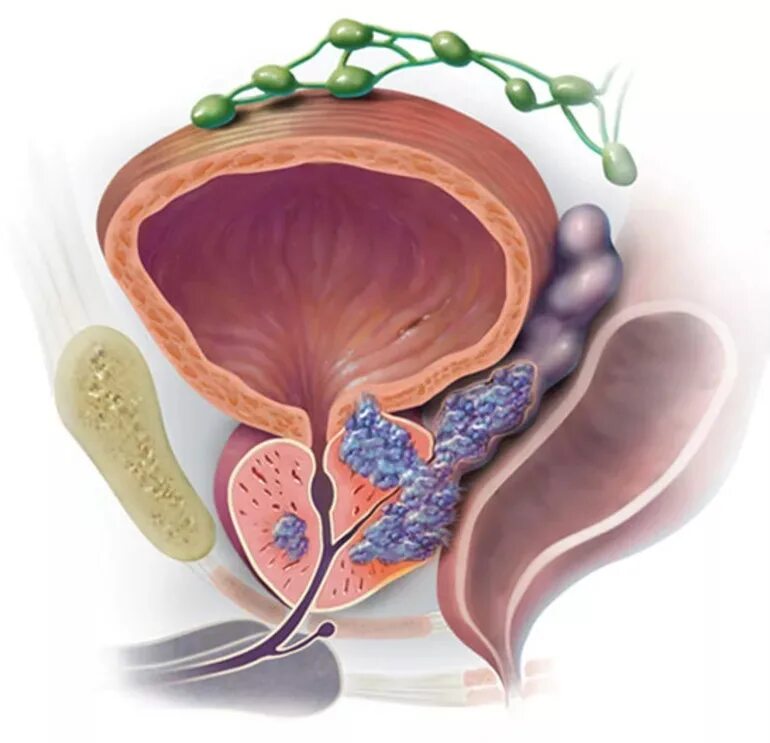

Аденокарцинома предстательной железы. Аденома простата железа. Злокачественное новообразование предстательной железы. Аденома и аденокарцинома

Аденокарцинома предстательной железы. Аденома простата железа. Злокачественное новообразование предстательной железы. Аденома и аденокарцинома Опухоль предстательной железы. Онкология предстательной железы

Опухоль предстательной железы. Онкология предстательной железы Опухоль предстательной железы. Кальцинаты в простате мрт. Опухоль предстательной железы у мужчин

Онкология предстательной железы. Предстательная железа презентация. Презентация онкология предстательной. Предстательная железа rak Предстательная железа в пожилом возрасте. Простатит 3 степени 2 класс. Метастазы простата рисунок

Предстательная железа в пожилом возрасте. Простатит 3 степени 2 класс. Метастазы простата рисунок Новообразование предстательной железы. Хирургическая капсула простаты. Tumor предстательной железы. Объемное образование в простате

Гистологическая классификация опухолей предстательной железы. Простатическая интраэпителиальная неоплазия. Опухоли предстательной железы факторы. Предраковые заболевания предстательной железы Злокачественное новообразование предстательной железы. Метастазы предстательной железы. Карцинома предстательной железы. Злокачественные новообразования простаты

Злокачественное новообразование предстательной железы. Метастазы предстательной железы. Карцинома предстательной железы. Злокачественные новообразования простаты Новообразование предстательной железы. Объемное образование предстательной железы. Злокачественная опухоль предстательной железы. Отёк предстательной железы